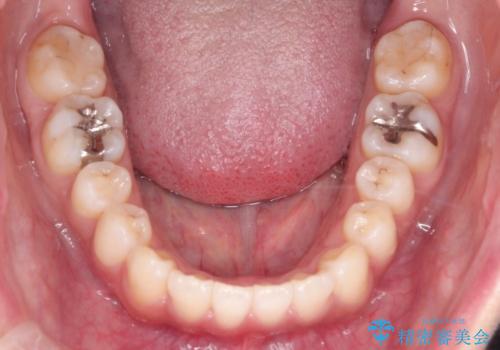

初診時の歯並びの状態としては、上下ともに全体に及ぶの中等度のがたつき(叢生)があり、全特に左上の前歯は1本だけ引っ込んでいる状態でした。

抜歯は行わず上顎の奥のスペースを利用して歯をスライドする方法の他に歯列弓の拡大やディスキング(歯と歯の間の隙間を作る処置)を行い叢生を改善しました。

歯の大きさの不揃いが原因の正中のズレは、ディスキング量を調整することで合わせました。